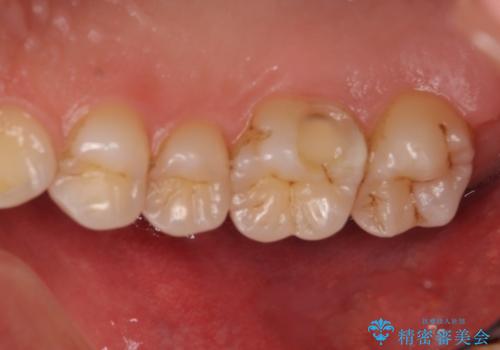

今回は虫歯が大きかったものの、ぎりぎり神経に達しておらず、セラミックインレー(つめもの)の治療のみで完了しました。初診時に虫歯を除去し、後日神経のテストをして正常反応を確認しました。

自分の歯や神経をなるべく残すには保険外治療をおすすめしています。